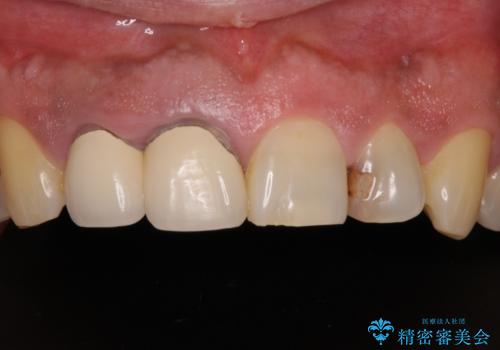

前歯の審美歯科治療 下顎の部分矯正と上顎前歯のオールセラミッククラウン

痛みが消えた後に、より目立たない装置をご希望とのことで、下顎前歯の舌側矯正で部分矯正を行い、歯列が整い、上顎前歯歯根部の病変が消退したことを確認した上で、上顎前歯をオールセラミッククラウンにて補綴治療を行うこととしました。

前歯部の見た目を改善するために、様々な医院を巡られたそうですが、当院ご提案のプランにて、痛みもスッキリと引いた、満足のいく仕上がりとなりました。